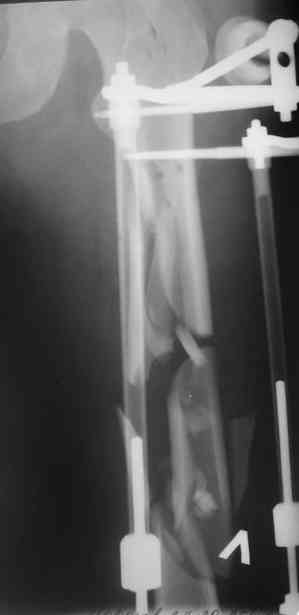

Лучше бы уточнить характер повреждения наружного мыщелка бедра, есть ли его фронтальное раскалывание. Мы бы сделали репозицию мыщелка (если получится, то закрыто) с фиксацией спонгиозными винтами.

Не получится закрыто - наружный парапателлярный доступ, открытая репозиция, винты. И сделали бы закрытый интрамедуллярный остеосинтез бедра антгерадно. Если есть возможность, лучше использовать гвоздь, который позволит провести винты через мыщелок, т.е. очень близко к

дистальному концу.

Вполне возможен и ретроградный остеосинтез бедра, особенно если все-таки придется открывать сустав.

Мышелок бедра репонировать открыто (степень открытости по ситуации) ввести гвоздь ретроградно, мышелок зафиксировать блокирующими винтами плюс дополнительно метафизарными при установленном гвозде.

После окончательного заживления раны снять аппарат наложить вытяжение дней на 5-7, посмотреть как ведут себя раны от стержней. Одномоментное снятие аппрата с забиванием гвоздя чревато, сколько, кстати он уже стоит?

Выждав, немного, сделал бы антеградный интрамедуллярный остеосинтез. Насчет того, чтобы винты, фиксирующие мыщелок являлись одновременно блокирующими не согласен - далековато гвоздь забивать придется. Хотя не уверен на 100%